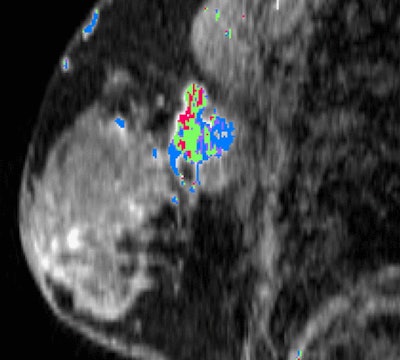

California researchers have found links between the appearance of triple-negative breast cancer on two different imaging modalities, MRI and PET/CT. They believe their findings can help guide therapy for the disease, which occurs less frequently but is typically more deadly than other types of breast cancer, according to a study published online July 22 in Radiology.

Researchers from the University of California, San Francisco (UCSF) found a strong association between dynamic contrast-enhanced (DCE) MRI signal enhancement ratio and maximum standardized uptake values (SUVmax) from PET/CT scans. The relationship could help illustrate the progression of triple-negative breast cancer and be a valuable tool to assess a patient's prognosis, they concluded.

Because DCE-MRI and FDG-PET/CT can visualize the functional properties of breast tumors, the modalities have increasingly been used to evaluate invasive breast cancer. DCE-MRI, for example, can quantify tumor progression through signal enhancement ratios, while SUVmax as measured by FDG-PET can indicate breast cancer metabolic activity.

Signal enhancement ratio (SER) was calculated by comparing early-to-late signal enhancement on a per-voxel basis. Voxels with SER values between 1.3 and 1.75 and greater than 1.75 displayed high washout and very high washout kinetics, respectively. Voxels with SER values from 0.7 to 1.0 and 1.0 to 1.3 showed low to medium washout kinetics, respectively. Voxels with SER values from 0.0 to 0.7 were deemed as low washout.